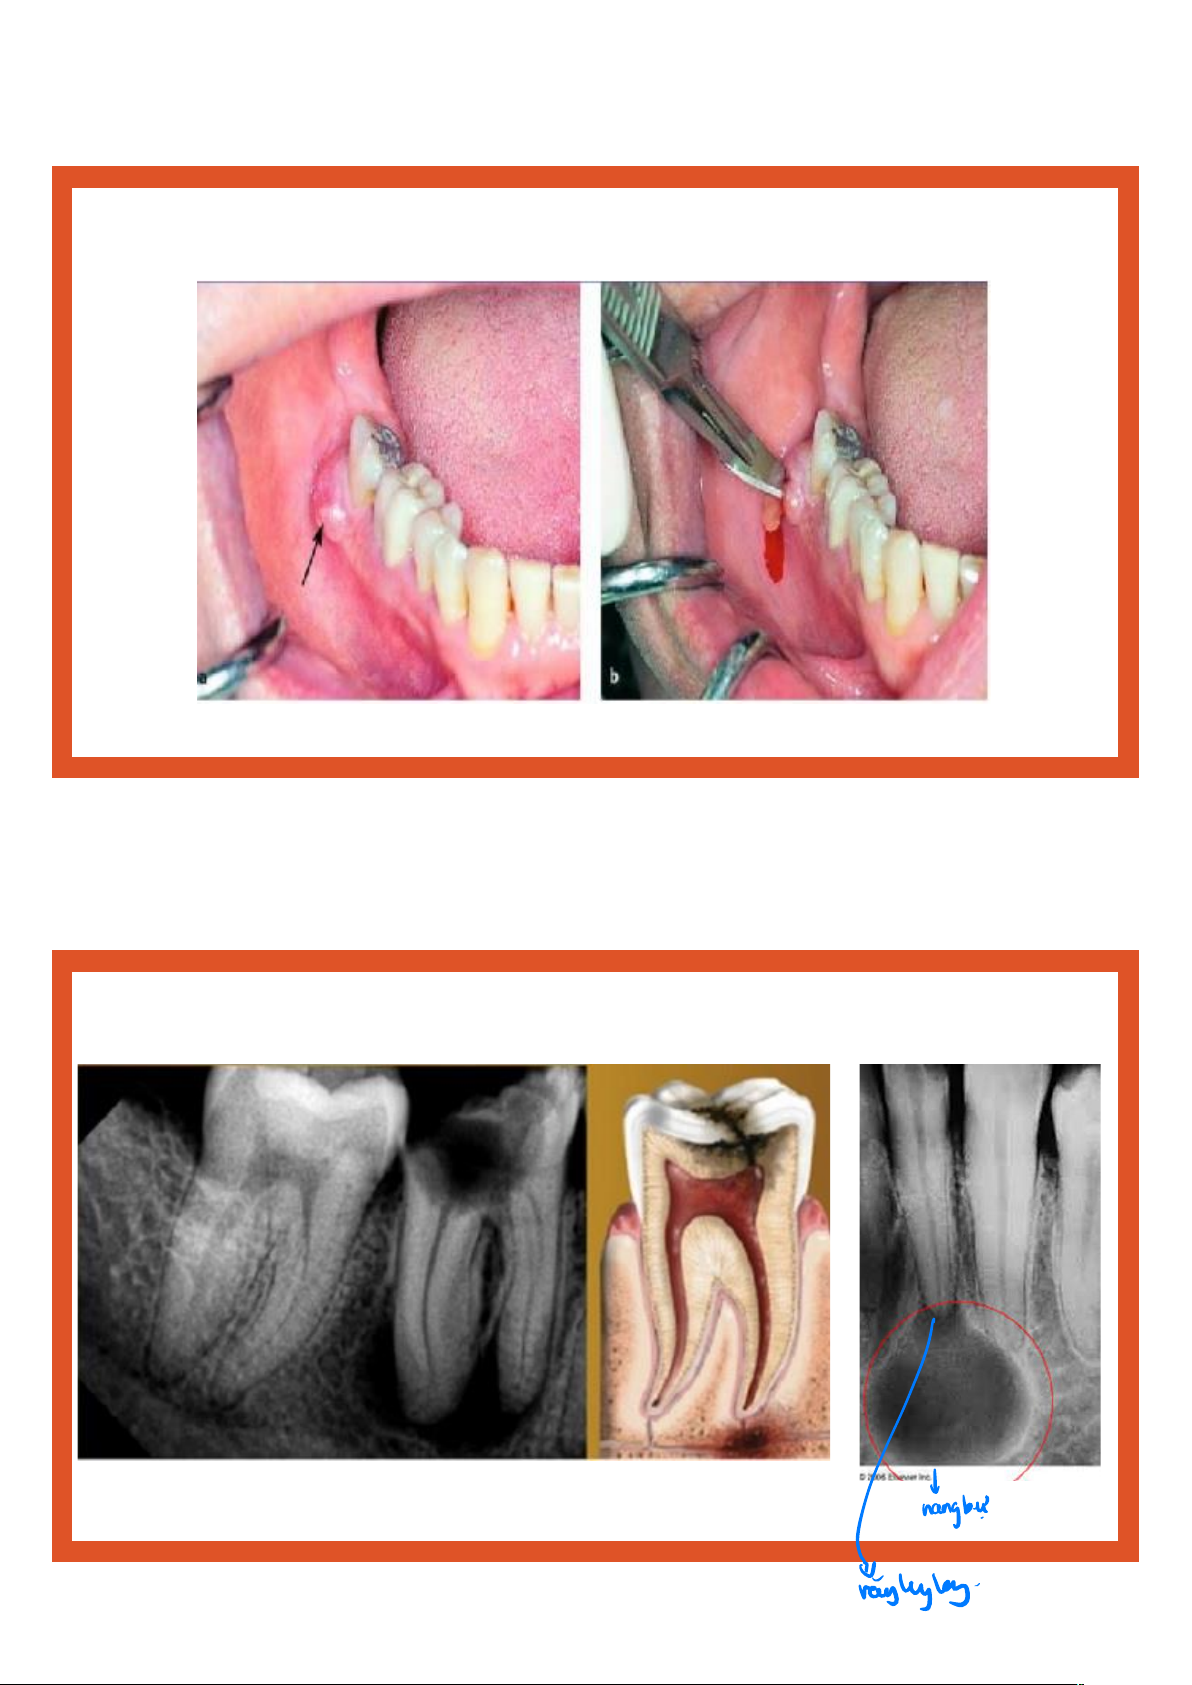

• Thử tuỷ (lạnh, điện) âm tính hoặc khám không đau. Biến chứng • Viêm quanh chóp cấp • Viêm quanh chóp mạn • Abces quanh chóp • Viêm xương • Viêm cốt tủy xương • Viêm mô tế bào • Viêm xoang hàm

• Viêm tắc tĩnh mạch xoang hang Phim quanh chóp